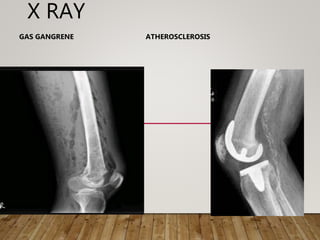

3. X ray: atherosclerosis , aneursym,

gas –gas gangrene, bone erosion in gangrene

X RAY

GAS GANGRENE ATHEROSCLEROSIS

INVESTIGATION 1. Blood: routineexamination WR – Syphilis sugar- diabetes, TG, cholesterol. urea, electrolytes 2. Urine: sugar , renovascular insufficiency 3. X ray: atherosclerosis , aneursym, gas –gas gangrene, bone erosion in gangrene 4. ECG- Cardiac status 5. USG – ABDOMEN 6. Pus - culture

X RAY GAS GANGRENEATHEROSCLEROSIS